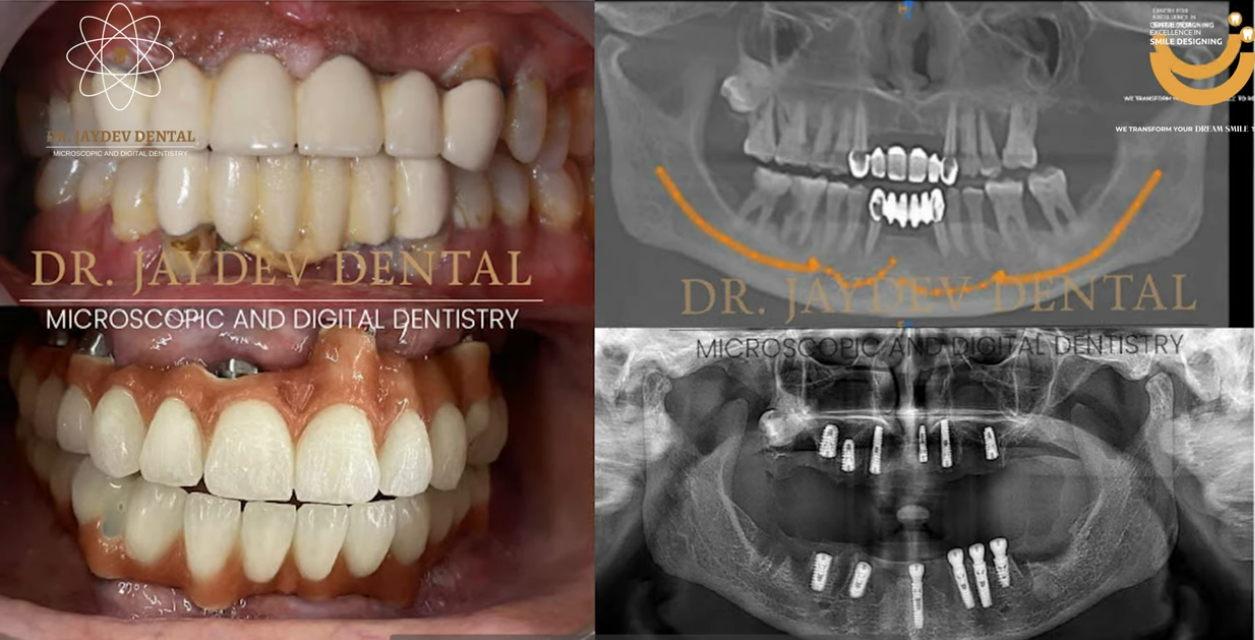

A patient came to us with advanced periodontal disease, a condition where the supporting structures of the teeth progressively deteriorate. Over time, this leads to gum recession, bone loss, tooth mobility, and ultimately tooth loss.

The patient’s primary concerns were difficulty in chewing, discomfort while eating, and a significant loss of confidence due to compromised oral health. Clinical examination confirmed multiple non-restorable teeth with severe bone loss.

- All-on-6 in the maxilla

- All-on-6 in the mandible

A total of twelve implants were placed with precise angulation and depth control.

After a healing period of approximately 3–6 months, during which osseointegration occurred, the implants fused successfully with the jawbone.

The final restoration provided structural support, aesthetic harmony, and functional efficiency.